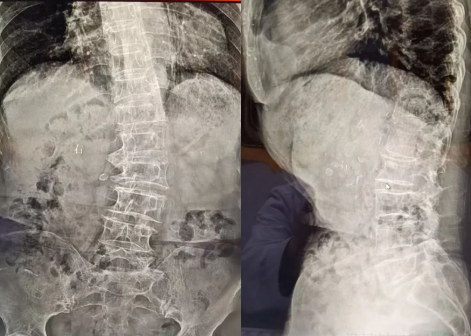

据悉,刘女士4年前无明显诱因腰部出现疼痛,因疼痛尚可忍受,刘女士未引起重视,疏于休息,且一直未行特殊治疗,不适症状逐渐加重。每逢受凉、劳累后上述症状加重。于半年前刘女士双下肢出现疼痛,右下肢症状更为明显,行走约300米,腰部及双下肢疼痛加重,每逢疼痛明显时,刘女士口服止痛药以及外用膏药,当时疼痛有所减轻,但停用后不适症状再次出现,并且日常活动也受到限制,已经严重影响到生活。多方打听后,刘女士经家中女婿介绍找到我院骨科杜华主任,要求系统治疗,门诊经询问、查体后拟以“腰椎间盘突出症”收入我院骨科。

杜华主任介绍“腰椎是脊椎的重要组成部分,它承担着我们身体上半身的重量,协调着下半身的运动,腰椎间盘突出症主要是突出的髓核组织,压迫了脊髓、神经,而引起下肢疼痛、麻木、肌力下降等症状……通过腰椎间盘射频消融术和小针刀治疗,并配合营养神经、抗炎止痛、针灸及物理治疗,第二天患者疼痛基本消除,出现全身从未有过的轻松,步行及活动也正常了,目前患者病情明显好转,精神矍铄。多年的腰痛一下解除,患者非常感激。